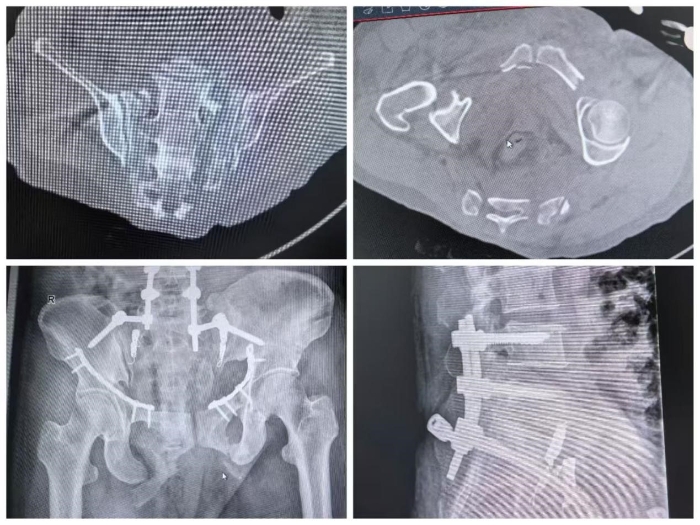

骨盆解剖結(jié)構(gòu)特殊,此類(lèi)損傷死亡率高達(dá)5%-16%,病情瞬息萬(wàn)變?;謴?fù)骨盆的穩(wěn)定性,避免骨折斷端對(duì)周?chē)浗M織和血管的二次損傷,控制出血、穩(wěn)定血流動(dòng)力學(xué)是搶救的首要目標(biāo)。14時(shí)12分,患者被緊急送入ICU進(jìn)行高級(jí)生命支持與術(shù)前準(zhǔn)備。多學(xué)科評(píng)估后一致認(rèn)為,必須立即恢復(fù)骨盆力學(xué)穩(wěn)定性,以減少骨折端活動(dòng)對(duì)周?chē)苌窠?jīng)的繼發(fā)損傷。14時(shí)43分,患者接受緊急“骨盆閉合復(fù)位外固定架固定術(shù)”,手術(shù)順利,術(shù)后返回ICU。

然而,患者血紅蛋白仍進(jìn)行性下降,多學(xué)科再次討論認(rèn)為盆腔仍有活動(dòng)性出血,經(jīng)CT檢查排除了其他實(shí)質(zhì)性臟器破裂。7月18日,血管外科主任張恒帶領(lǐng)團(tuán)隊(duì)進(jìn)行了DSA引導(dǎo)下“雙側(cè)髂內(nèi)動(dòng)脈栓塞術(shù)”,成功實(shí)現(xiàn)搶救性止血,患者生命體征漸趨平穩(wěn)。在ICU的精心治療下,患者艱難渡過(guò)危險(xiǎn)期,于7月29日轉(zhuǎn)入骨科進(jìn)行后續(xù)專(zhuān)科治療。

針對(duì)其Tile C型(垂直不穩(wěn)定)骨盆骨折,副院長(zhǎng)馬剛組織團(tuán)隊(duì)進(jìn)行了深入的術(shù)前討論。為爭(zhēng)取最佳功能預(yù)后,需盡早施行手術(shù),實(shí)現(xiàn)解剖復(fù)位與堅(jiān)固固定。團(tuán)隊(duì)制定了周密方案——以后路腰髂螺釘固定糾正骶骨垂直移位,并采用改良Stoppa前路入路,單一切口完成雙側(cè)恥骨上下支骨折的切開(kāi)復(fù)位內(nèi)固定,最大程度減少手術(shù)創(chuàng)傷。

8月5日,馬剛帶領(lǐng)團(tuán)隊(duì)成功為患者進(jìn)行了“骨盆骨折切開(kāi)復(fù)位后路腰髂螺釘固定+前路改良Stoppa入路鋼板內(nèi)固定術(shù)”。術(shù)后影像顯示骶骨垂直移位完全糾正,骨折對(duì)位及內(nèi)固定位置極佳,手術(shù)獲得圓滿(mǎn)成功。經(jīng)過(guò)后續(xù)系統(tǒng)康復(fù),患者恢復(fù)良好,順利出院。